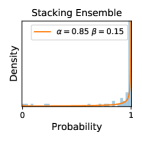

5.1 Distribution of Uncertainty Scores

Distribution of Uncertainty Scores Across Different Severity Levels As explained in Section 3, each uncertainty metric essentially defines an order/ranking among the data points. We conducted an analysis to better understand what data will be assigned high uncertainty under a particular uncertainty metric . Picking out the highest ranked data points (), we calculated the ratio of data points from each SL. Figure 4 summarizes the results as box plots for the Kaggle-DR and the Messidor-2 datasets; additional detailed statistics can be found in Table S.1 in the supplementary materials. From the plot and table, SL1 & SL2 examples account for a higher proportion among the top-ranked uncertain examples across the three ensemble methods. This finding matches our intuition that incipient disease examples (SL1 & SL2) are more likely to be considered uncertain by ensemble methods due to their ambiguity.

In contrast, the MC-dropout method showed the worst overall performance among the three, as it can be seen from the high ratios of SL0 examples among the uncertain negatives in Figure 4. The histograms in Figure 2 provides another perspective to look into the phenomenon, where a decent proportion of MC-dropout model’s predictions on SL0 inputs entailed low confidence (far from 0 or 1), which from another angle explained why MC-dropout was less specific in terms of lower FNP; many no-DR inputs (i.e. SL0) were erroneously assigned high uncertainty by MC-dropout models.

It is still an open question why the evaluated MC-dropout networks signaled relatively high uncertainty on SL0 & SL3 & SL4 data that are less likely to be ambiguous. We conjecture that much of the “uncertainty” indicated by disagreement among test-time dropout samples actually reflects the stochastic nature of dropout networks rather than the real decision uncertainty associated with the data. It is worth noting that the MC-dropout model we evaluated was not weak per se; they all achieved above Area Under Curve (AUC) scores on test sets. The weakness of individual test-time samples (which explains their low-confidence predictions on SL0 & SL3 & SL4) might have been hidden when they are aggregated into an ensemble—a well-known advantage of ensemble learning. Our results suggested that the uncertainty information given by implicit ensemble methods such as MC-dropout and TTA might not be as reliable as that from explicit ensemble approaches (e.g., stacking ensembles). Similar findings on MC-dropout can be found in some previous papers [1].